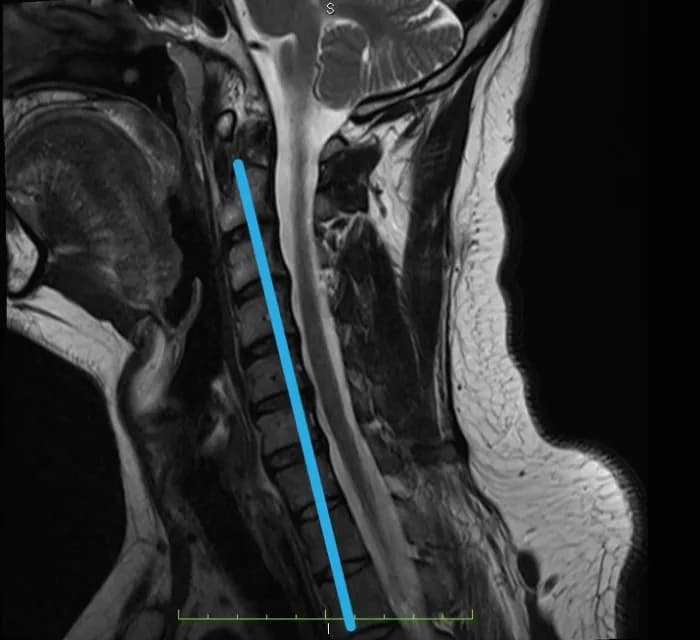

Skręcenie karku: poznaj objawy, przyczyny i pierwszą pomoc przy urazie szyi. Dowiedz się, kiedy na SOR i jak wygląda leczenie oraz rehabilitacja.